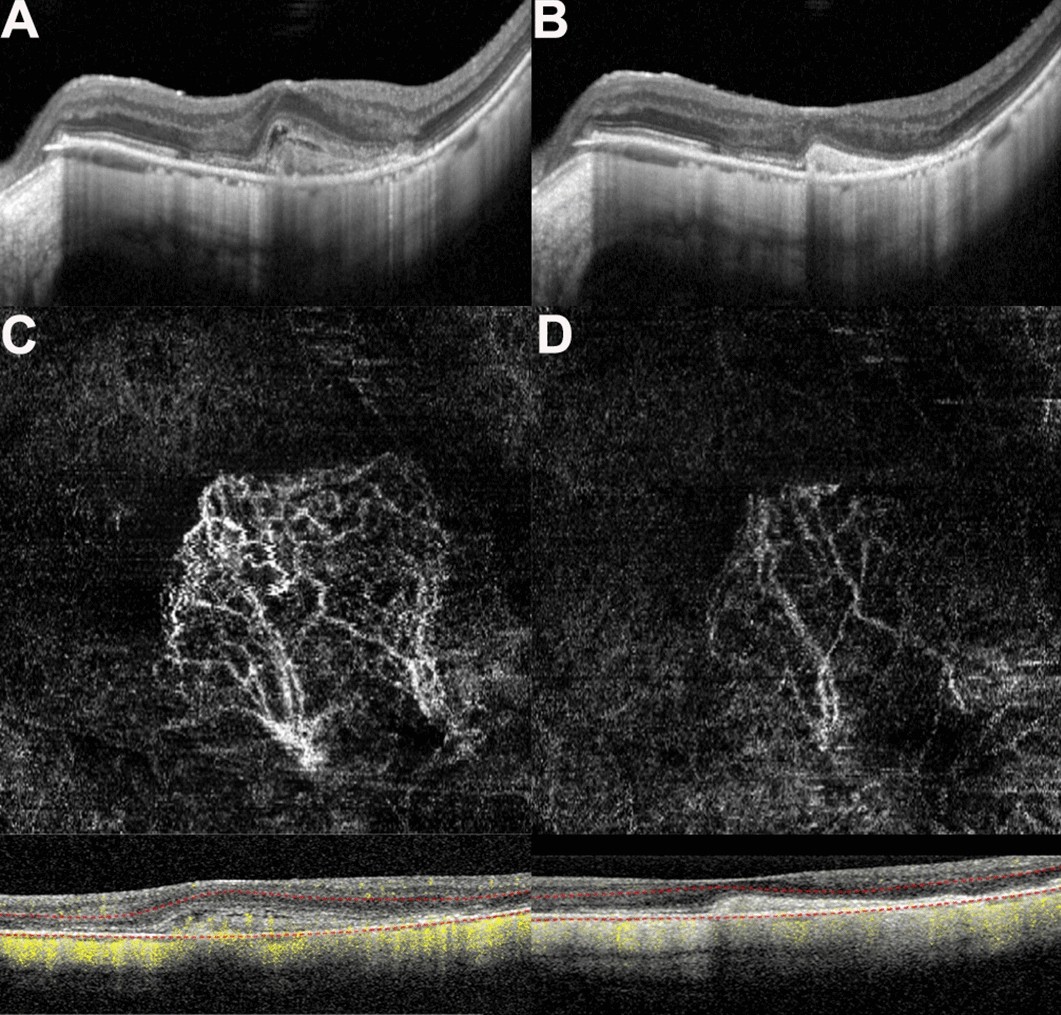

Figure 3

(A,B) Optical coherence tomography (OCT) images of a patient with myopic macular neovascularization (mMNV) before and after receiving conbercept. Central macular thickness (CMT) decreased from 371.43 to 248.98 μm. The hyperreflective signal lesions in the outer layer of the retina shrank and the outer structure tended to normalize. (C,D) Optical coherence tomography angiography (OCTA) images of the patient before and after injection. (C) Presents a large-area, highly organized, interlaced high-flow MNV vascular network. It contains small capillary branches and nourishing blood vessels and is surrounded by a low-signal halo, showing a leafy tree crown or sea fan shape. One month after conbercept treatment, the MNV of (D) shows only nourishing blood vessels with larger diameters, the small blood vessels decreased or even disappeared, the blood vessels intertwined, and the blood flow was significantly reduced. The MNV areas in (C) and (D) are 2.69 and 1.08 mm2, while the blood vessel areas are 0.92 and 0.24 mm2, respectively.